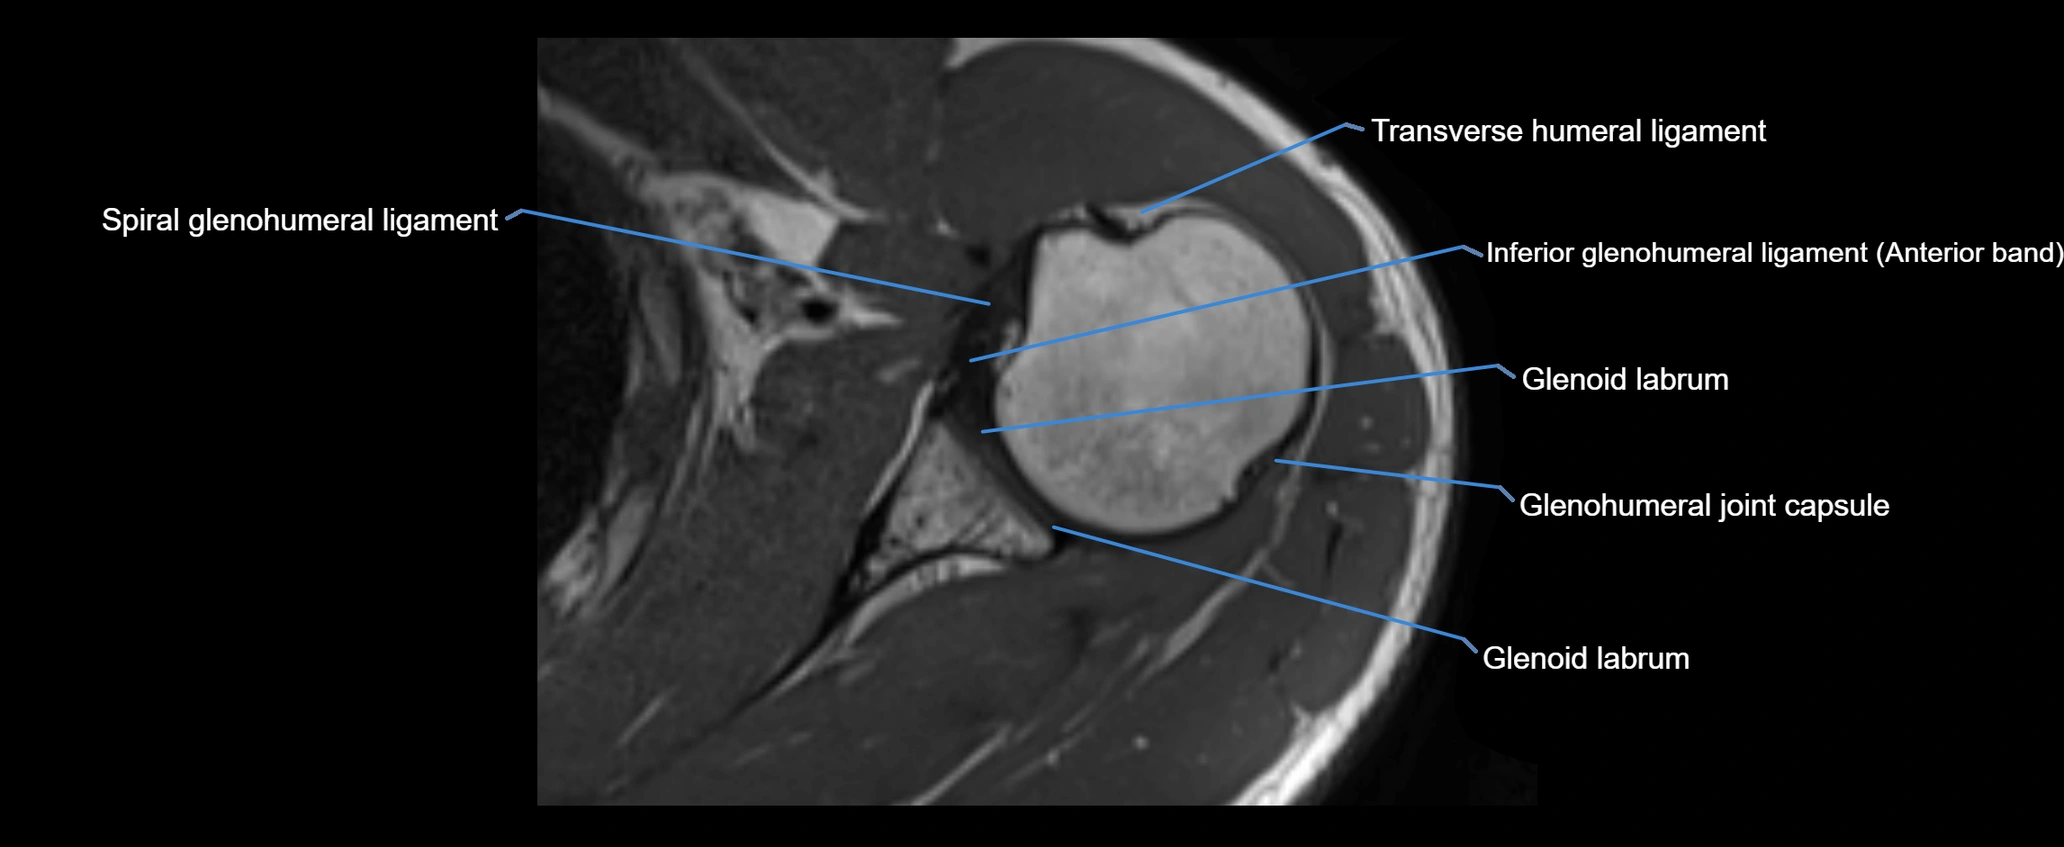

CT image

image